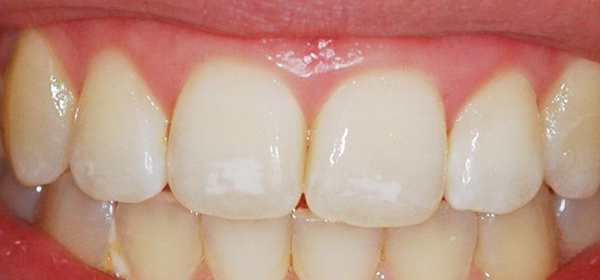

- Пятнистая: на поверхности образуются пятна сероватого или беловатого цвета. Пятна могут сливаться и образовывать одно большое. Поверхность гладкая и блестящая, отсутствуют чёткие границы, они плавно переходят в здоровые участки.

Фото 2. Эндемическая форма флюороза, равивается по причине повышенного содержания фтора в питьевой воде.

Фото 3. Штриховая форма флюороза, эмаль слегка пятнистая, с несильно выраженными бороздками.